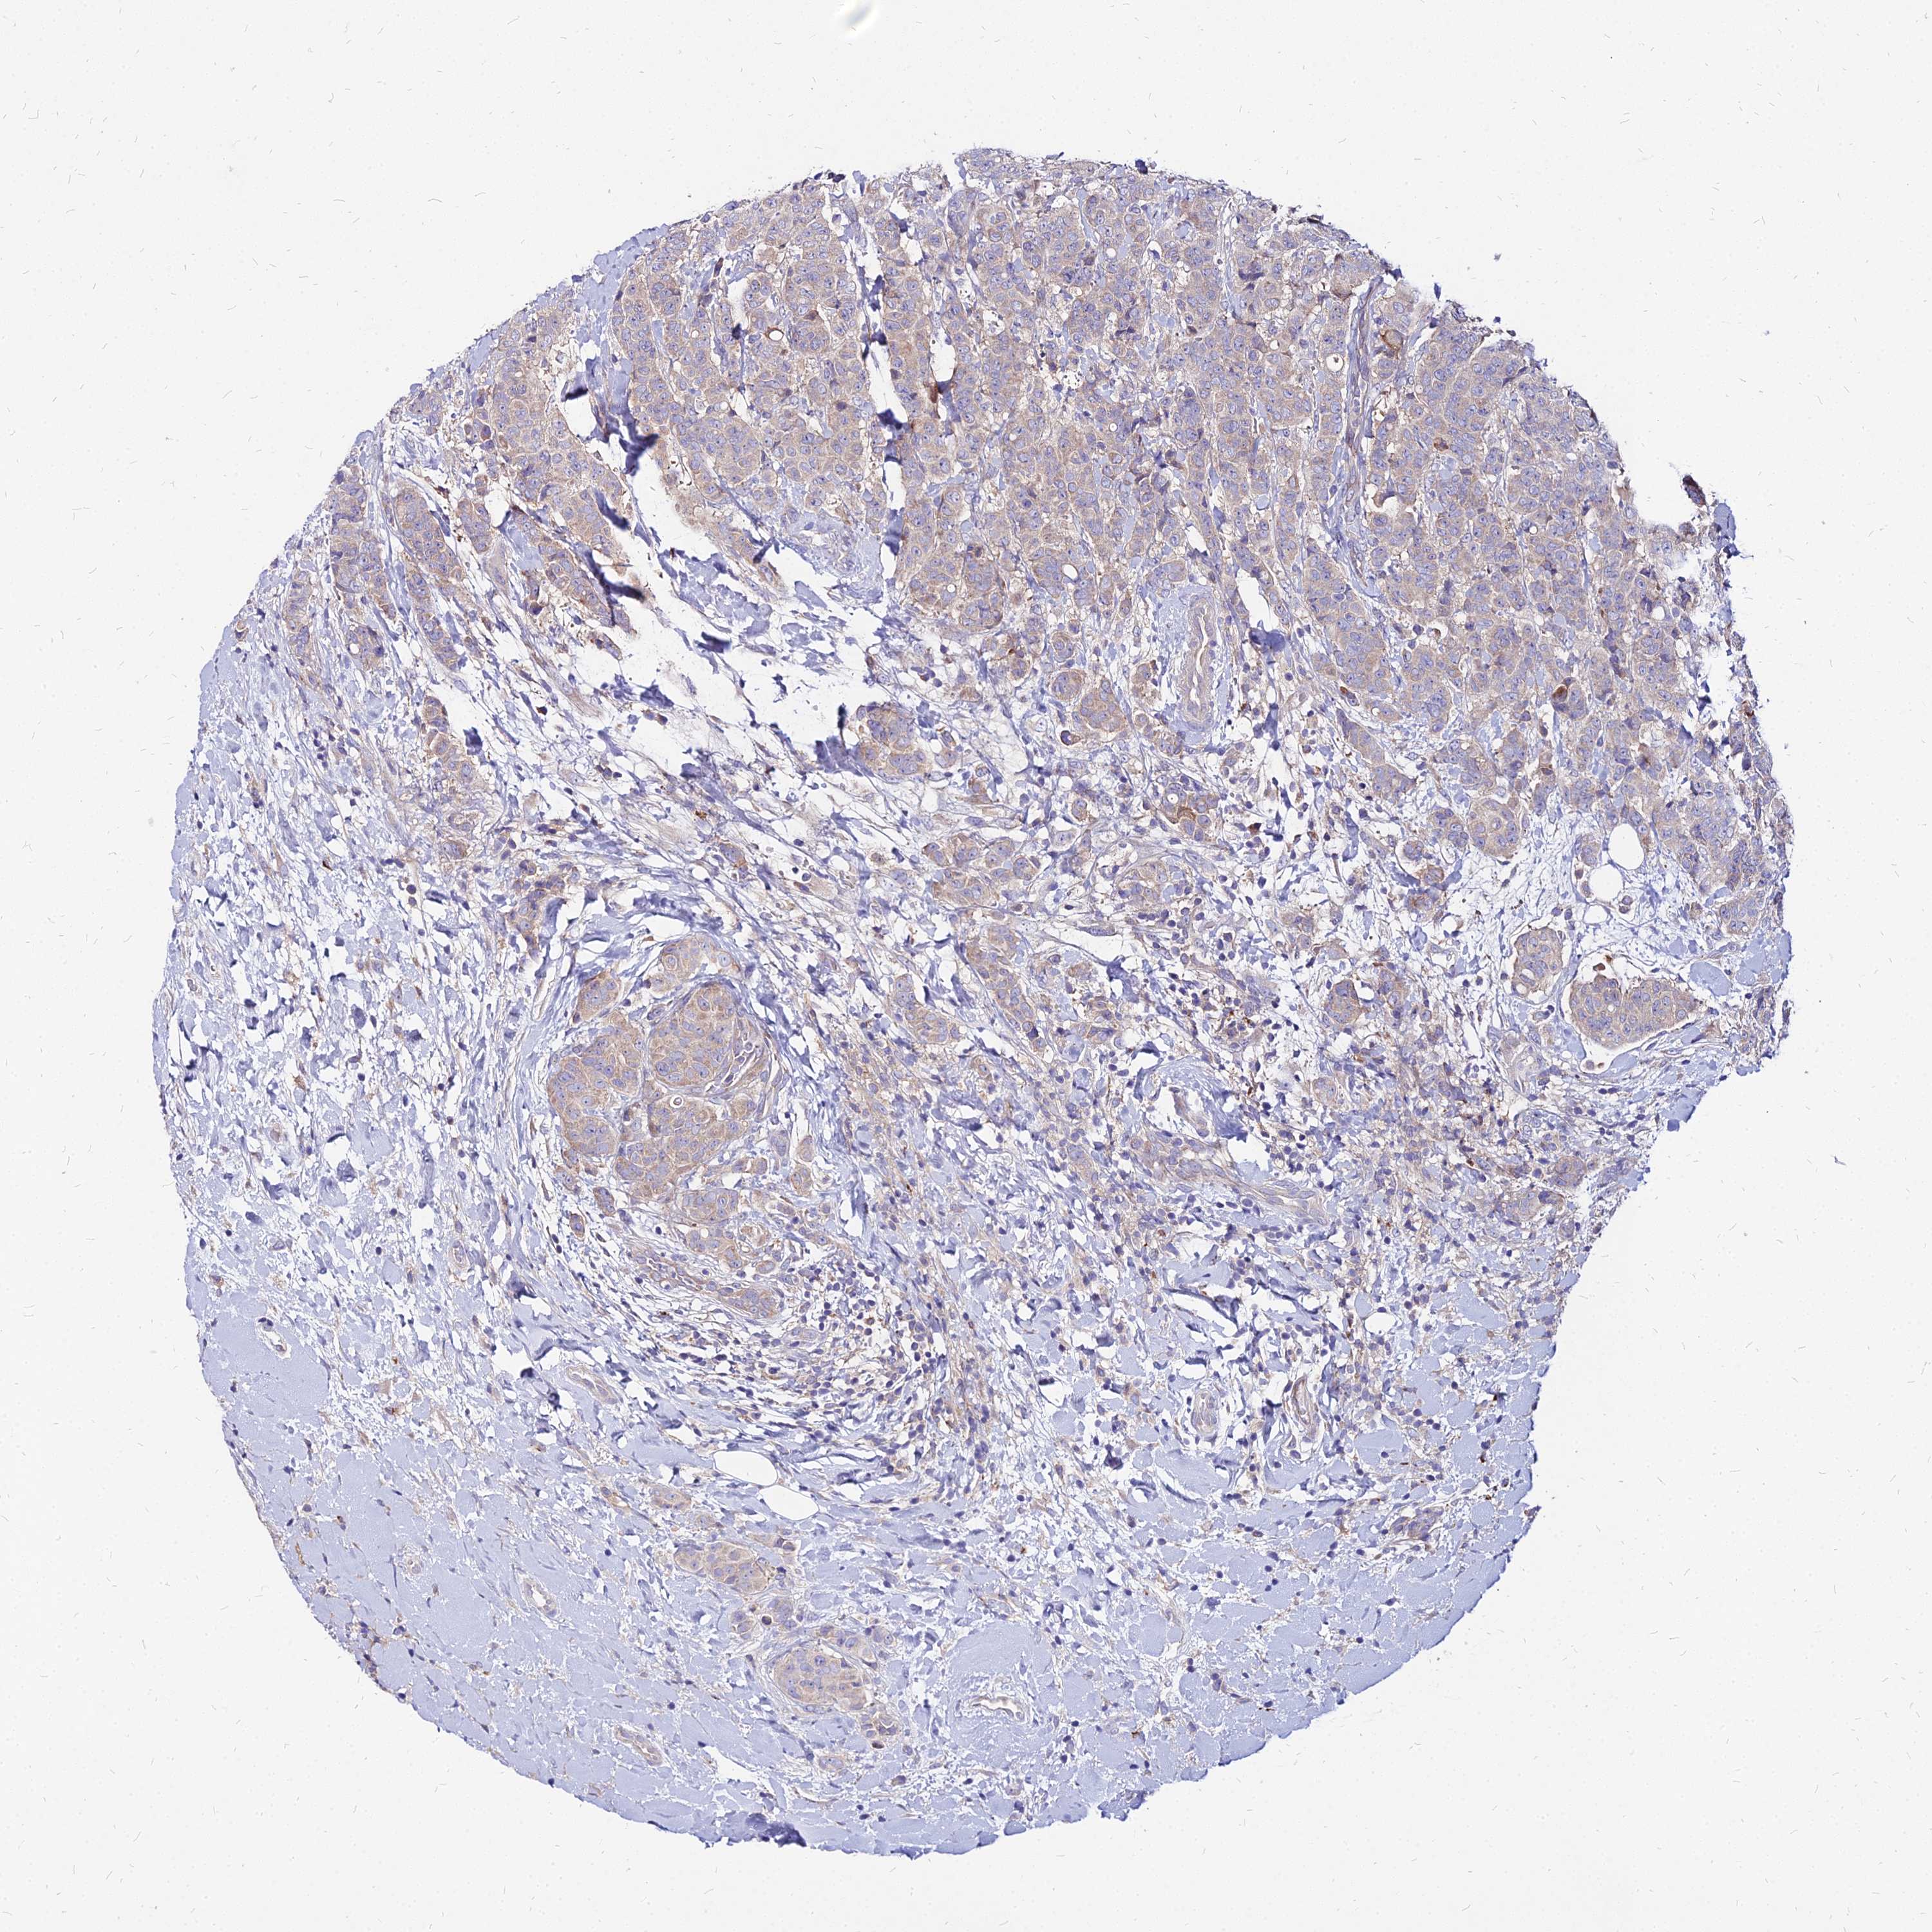

CANCER BREAST CANCER Show tissue menu

BRCA TCGA BRCA VALIDATION PROTEIN EXPRESSION